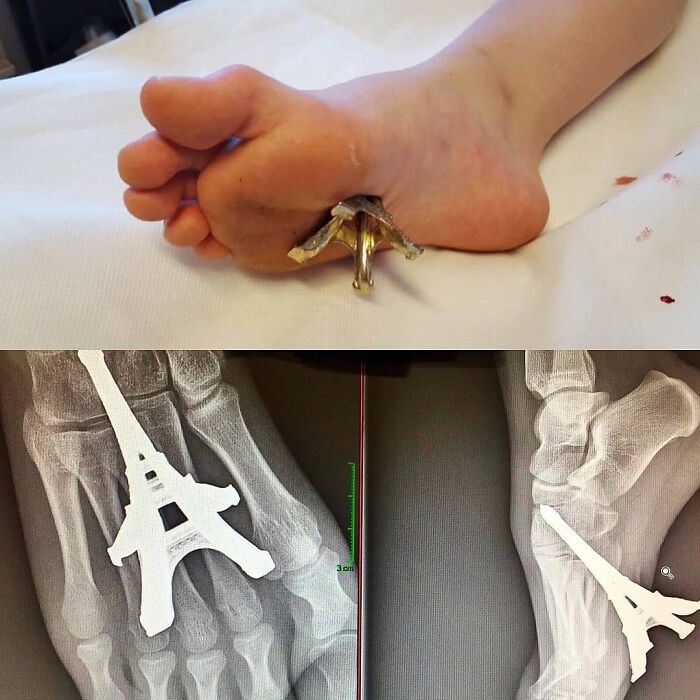

#30 “Ei-Ffel”. This Is The Actual Photo Of Yesterday’s Case Showing An Eiffel Tower Miniature Embedded Into The Foot

Image source: medical_pedia